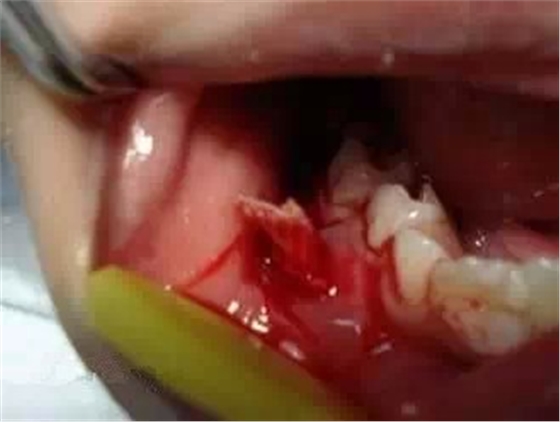

已形成粘膜下膿腫的還需在口腔內(nèi)的腫脹部位做局部切開排膿,而腫脹嚴(yán)重者,則需用碘仿紗條進(jìn)行引流。(醫(yī)大口腔醫(yī)院 高生輝老師圖片)

(以上圖片引用自福建醫(yī)大附屬口腔醫(yī)院兒童科 高生輝老師的課件,非常感謝!)